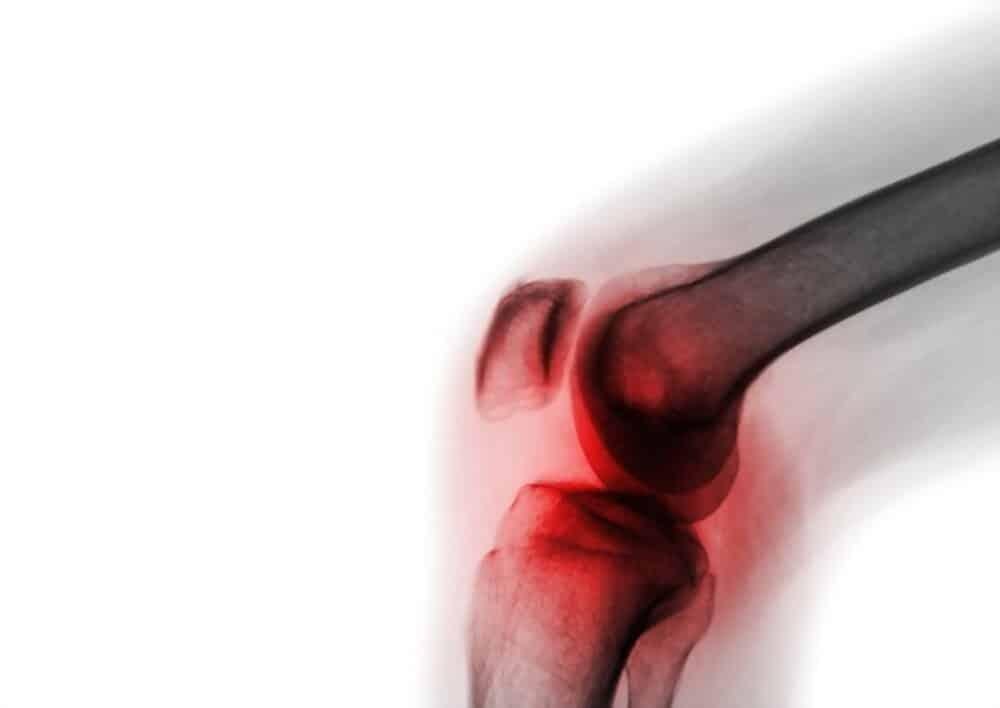

Viêm khớp nhiễm khuẩn là tình trạng nhiễm trùng bên trong khớp, tức là vi khuẩn xâm nhập vào khớp khiến khớp bị sưng tấy và đau. Viêm khớp nhiễm khuẩn hiếm khi xuất hiện ở nhiều khớp cùng lúc.

Những khớp dễ bị nhiễm trùng bao gồm: khớp gối, khớp hông, khớp cổ tay, khớp vai, khuỷu tay và khớp mắt cá chân.

Dấu hiệu của viêm khớp nhiễm khuẩn là khớp bị sưng nhanh, rất đau và khó hoạt động. Ngoài ra, các triệu chứng còn bao gồm sốt cao, ớn lạnh, run rẩy, đau cơ và mệt mỏi.